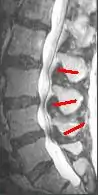

Helpful imaging may include x-rays, CT, CT myelogram, and magnetic resonance imaging (MRI), but MRI is preferred.[1] Abnormal MRI findings may be present in two-thirds of asymptomatic individuals, and imaging findings of spinal stenosis do not correlate well with symptom severity. Therefore, imaging findings must be considered in the context of a patient's history and physical exam when seeking a diagnosis.[2] The evidence for using objective imaging findings to define NC has been conflicting.[12]

Degenerative disc disease (DDD) may trigger the pathogenesis of neurogenic claudication. When intervertebral discs degenerate and change shape in DDD, the normal movements of the spine are interrupted. This results in spinal instability and more degenerative changes in spinal structures including facet joints, ligamentum flavum, and intervertebral discs. These pathologic changes result in narrowing of the vertebral canal and neurovascular compression at the lumbosacral nerve roots.[1][17] The compression of these spinal nerve roots that control sensation and movement in the lower body results in the tingling, pain and weakness NC patients often experience. However, because the severity of symptoms does not correlate well with the degree of stenosis and nerve root compression, a clear understanding of the specific pathogenesis remains challenging.[7]

These changes in blood flow may occur during back extension when shifts in vertebral structures and ligaments narrow the spinal canal and compress the neurovasculature.[15] Compared to a neutral position, extended spines exhibit 15% less cross-sectional area of the intervertebral foramina, and nerve root compression is present one-third of the time.[10] These dynamic changes in the shape of the spinal canal are more pronounced in individuals with spinal stenosis. The amount of narrowing may be 67% in LSS compared to 9% in healthy spines.[1]